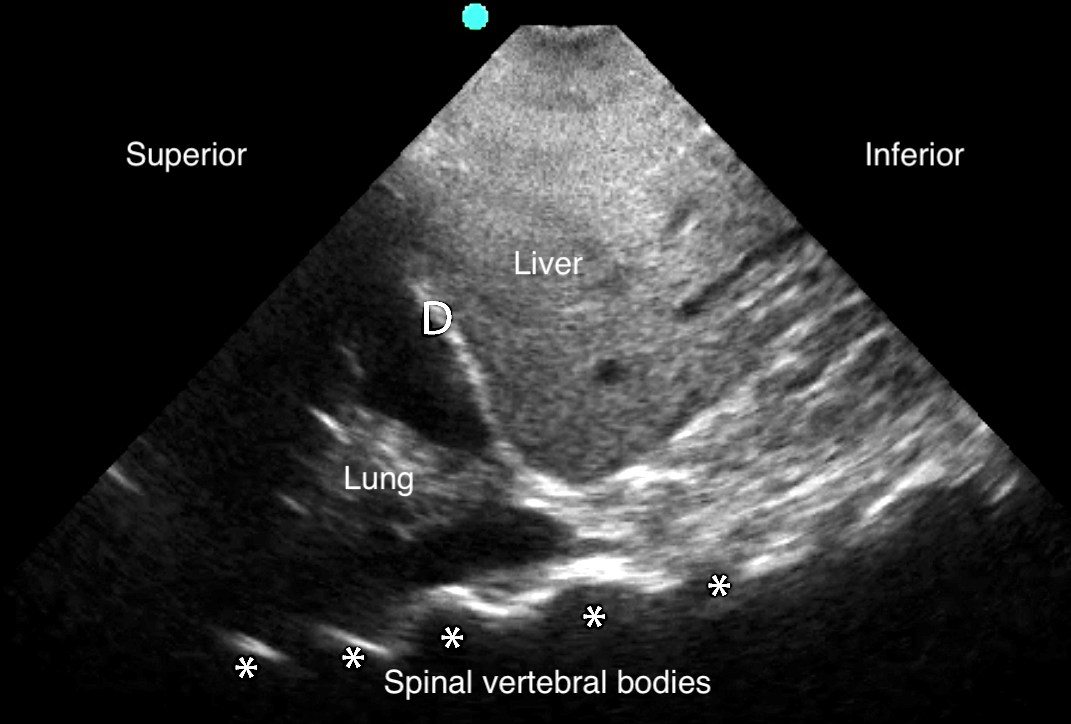

- Figure 18. Pleural effusion with spine sign

- Quad sign delineates four boundaries: superior and inferior rib shadows, superficial parietal pleura, and the deeper visceral pleura.

- Figure 19. Pleural effusion with quad sign